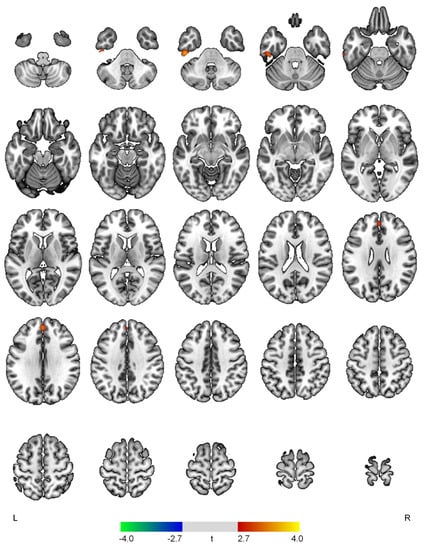

| Positive correlations with the hyperactivity domain | ||||

| L inferior temporal gyrus | 3.66 | <0.001 | 315 | −46, −26, −36 |

| Superior frontal gyrus | 3.30 | 0.001 | 171 | 0, 46, 32 |

| Negative correlations with the hyperactivity domain | ||||

| None | ||||

| Positive correlations with the psychosis domain | ||||

| R cuneus | 3.53 | <0.001 | 305 | 4, −76, 34 |

| Negative correlations with the psychosis domain | ||||

| R putamen | 4.06 | <0.001 | 921 | 26, 12, 0 |

| L inferior occipital gyrus | 3.64 | <0.001 | 131 | −30, −84, −4 |

| L middle frontal gyrus | 3.49 | 0.001 | 702 | −44, 24, 44 |

| L anterior cingulate gyrus | 3.46 | 0.001 | 350 | −14, 0, 42 |

| L inferior frontal gyrus | 3.30 | 0.001 | 368 | −34, 30, −6 |

| R precentral gyrus | 3.20 | 0.001 | 191 | 64, 10, 20 |

| L central operculum | 3.04 | 0.002 | 118 | −50, 4, 6 |